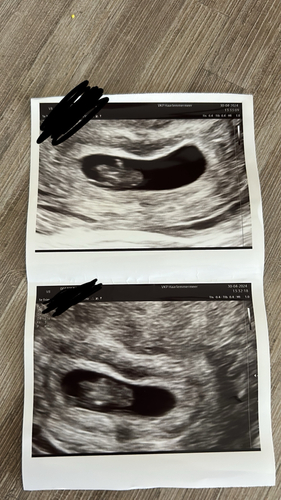

Vandaag echo gehad omdat er veel pijn links was dus vermoeden buitenbaarmoederlijke zwangerschap nu is dit gelukkig niet van toepassing. Echter verder weinig tot niets te zien behalve dat het in baarmoeder zit. En conclusie geschreven als

Verdenking IUG DD miskraam

Kortom stress over week terug deze week duurt nu al te lang. Voel me echt enorm aangeslagen